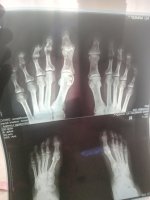

ومن الأشعة المرفقة اتضح ترسب tophi ويشتبة الإصابة بالنقرس ويجب عمل تحليل serum uric acid لتأكيد التشخيص

التحليل يبين ارتفاع شديد في معامل الالتهاب وسرعه الترسيب وارتفاع نسبه النقرس

مرحبا بك ، التحاليل تشير الي وجود ارتفاع بمعامل الالتهاب وسرعة الترسيب وارتفاع بنسبة حمض اليوريك بالدم والذي يدل علي الإصابة بالنقرس

وذلك سبب تورم القدمين والشعور بالألم اثناء السير والوقوف عليها